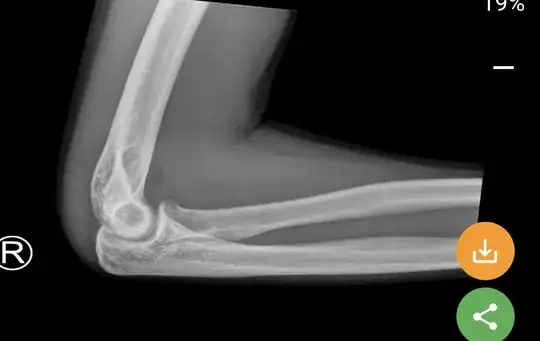

The Fracture is not an obvious one; there are occult fractures. The presence of a joint effusion, while not always associated with a fracture, is usually associated with a fracture when the history is consistent with an acute injury (possible fracture).

The radial head isn't grossly abnormal. There's a tiny suggestion of a possible fracture in the angularity of the radial neck. There 'should' be a bit of a smoother transition from the head to the radial shaft. However, it might not be called a fracture but for the presence of an effusion (in this case blood) in the joint capsule.

There are positive fat pad signs on the radiograph above.

If you look at the posterior humerus, you'll see a lucency all along the joint:

That's never present without an effusion. That's the posterior fat pad sign.

Without seeing more than one view, it's difficult to say where exactly the fracture is in the joint, but it's clear (if there's a history of recent trauma) that there's a fracture somewhere in the joint because of the two fat pad signs.